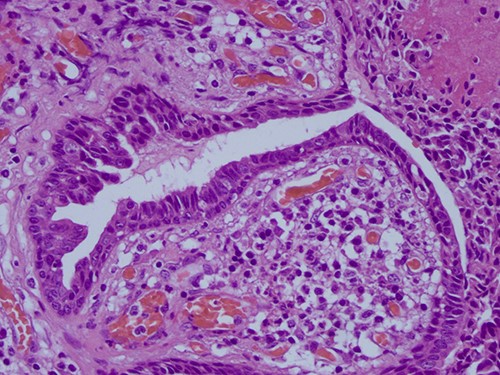

The histopathological examination found cystic invaginations of the infundibular epithelium projecting into the dermis, covered by a double cell layer (Fig. 2), proliferation of glands with prominent papillary architecture (Fig. 3) and fibrous cores containing numerous stromal plasma cells (Fig. 4). Other findings include verrucous (papillomatous) epidermal hyperplasia with hyperkeratosis and hypergranulosis (Fig. 5), irregular duct-like structures and cystic spaces (Fig. 6) and glands with double layer of cuboidal columnar epithelium and numerous stromal plasma cells (Fig. 7). These findings are compatible with Syringocystadenoma papilliferum with no signs of malignancy.

H&E staining 10× magnification. Proliferation of glands with prominent papillary architecture.